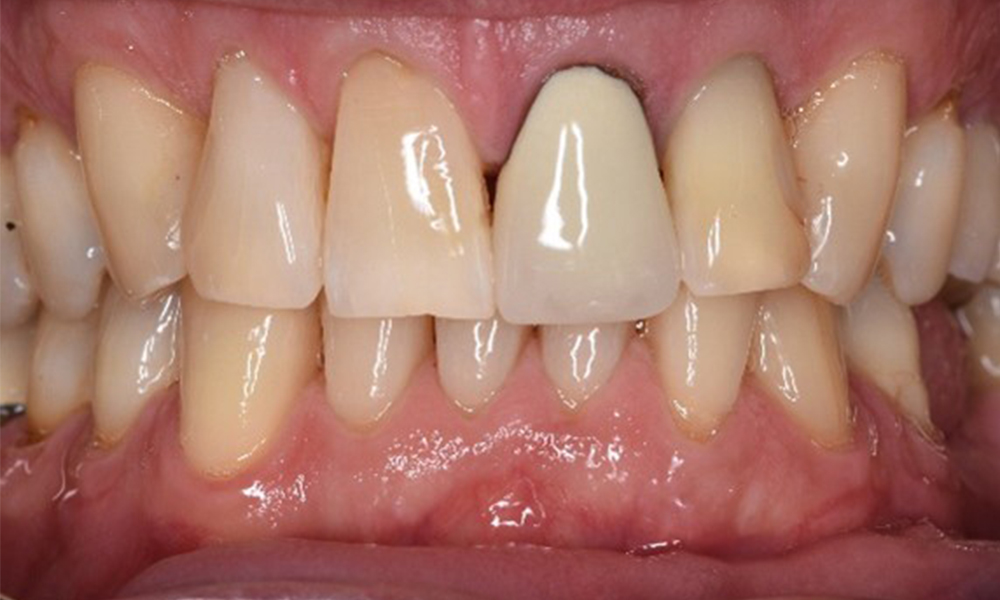

The (orally) healthy patient with implants

In the medical history, the 55-year-old patient states that he has no systemic disease and is not taking any medication. The patient’s lifestyle is similarly unremarkable. The patient has a few tooth restorations and two implants (2nd and 4th quadrants). On the basis of current findings, gingivitis is identified in an otherwise stable periodontal condition on the reduced periodontium (stage III, grade A). more